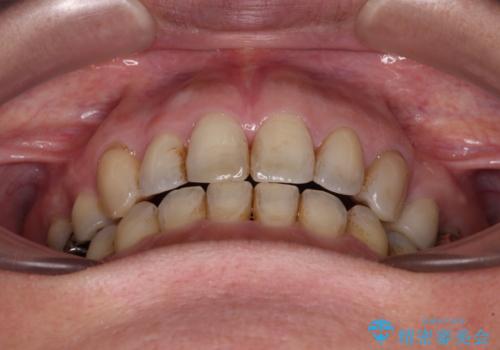

上顎左右第1小臼歯を抜歯したことで、隙間が閉じた下顎歯列の位置まで前歯を引っ込ますことができたため、口の閉じにくさを解消することができました。